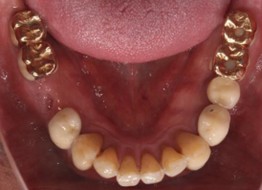

70代 男性

治療前

治療後

治療後- 年齢/性別

- 70代/男性

- 主訴

- 右上3/左上1~7/右下7~4/左下6

- 治療期間

- 12ヶ月

- 治療費

- インプラント¥3,960,000

骨造成¥330,000

サージカルステント¥187,000 - リスク・副作用

- 術後の腫脹 出血